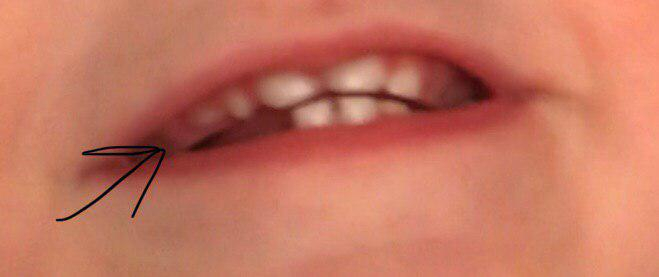

ЗубкиПодскажите, что с зубом? Это верхний боковой резец. Такое ощущение что он или кривой или там два зуба друг на друге? Такое бывает? Правая часть (остренькая) вылезла еще в декабре, а вот несколько дней назад вылезла левая часть зуба. Просто правый боковой резец вылез сразу весь и быстро, а этот вот так... Поэтому я не уверена что один и тот же... Что же это?...

Не пугайтесь, там на одной фотке черная грязь прилипла к одному зубу, с пола все подбирает и жрет)

12 повернут, не зватает места в в.ч. в верхней челюсти.

Нет, ребенку год и три месяца. 12 зубов всего, ну если это два зуба, то тогда 13. Снимок разве надо делать в таком возрасте?..это все так серьезно?

значит боковой резец вылез криво? это совсем прям плохо или со временем будет нормально (хотя бы когда коренные будут).